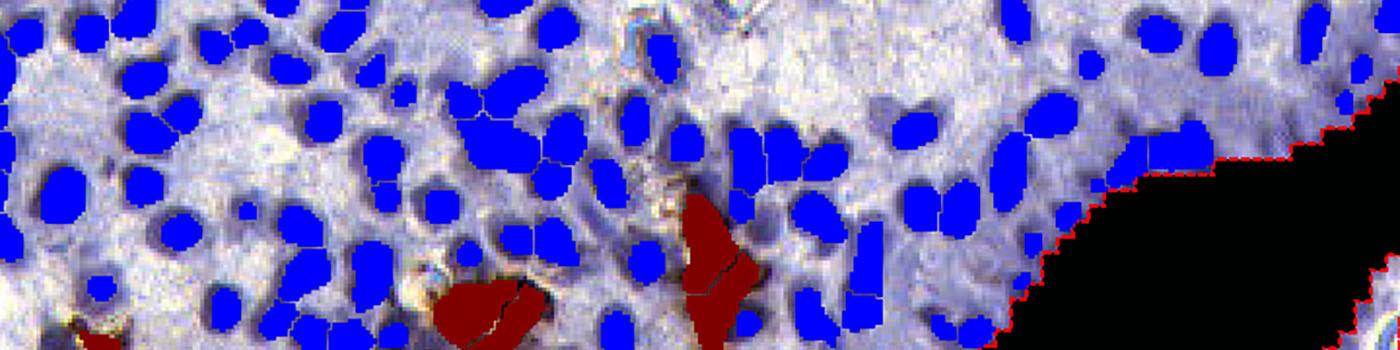

This APP measures the ratio of uNK cells among the stromal cells near the epithelial edge. Cells in the glands and in the epithelial edge itself do not contribute to the calculations.

Step 3: Load APP quantification protocol ’03 Count Cells’ and run on the images to process. The third image processing step identifies the uNK and stromal cells, within the specified ROI, and calculates the output variables.

The second step identifies the epithelial edge within the tissue based on saturation and local shape. It outlines a final ROI up to 300 µm into the tissue from the epithelial edge, still excluding glands (see FIGURE 1, 2, 3, 4).

The third step identifies uNK cells and stromal cells within the final ROI, and calculates the relevant output variables, including the ratio of uterine Natural Killer (uNK) cells to stromal cells (see FIGURE 5 and 6).